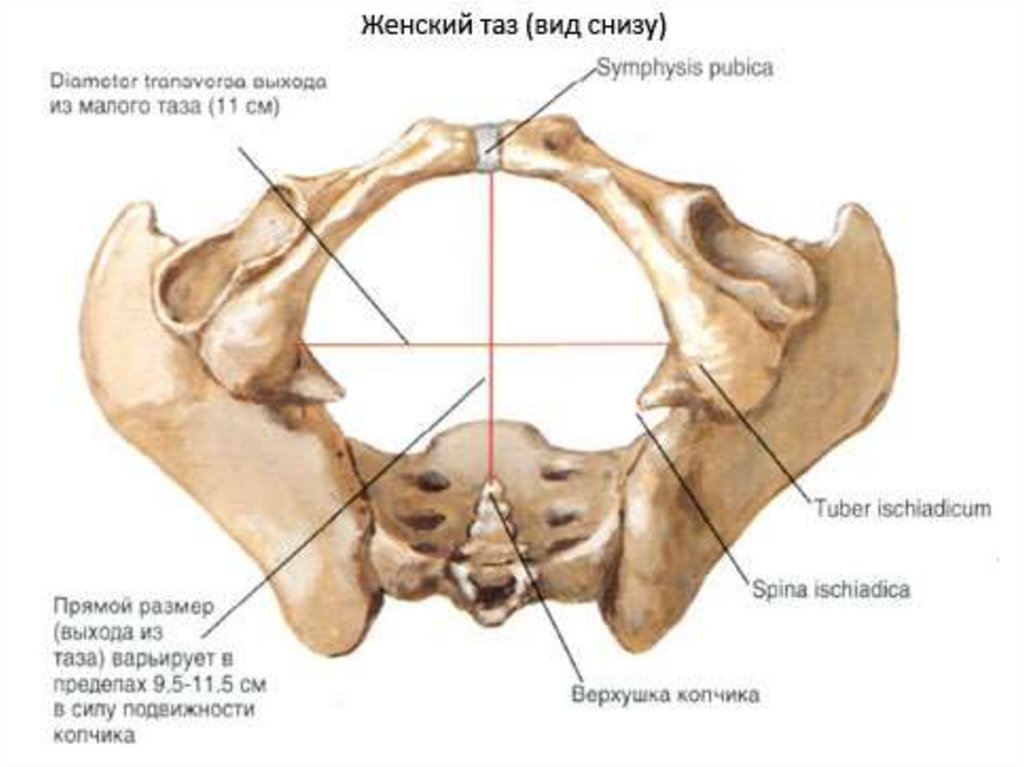

Анатомия малого таза: детальные схемы и изображения